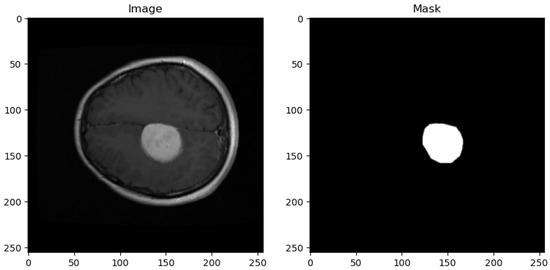

- Annotation Details: Each MRI image entry in the dataset is accompanied by essential information, including the class name (tumor type), patient ID, image data, tumor borders (defined by x and y coordinates outlining various points on the tumor’s boundary), and a binary tumor mask representing the segmented tumor area.

- Original Image: The pipeline receives the MRI scan as its initial input, showcasing a comprehensive cross-sectional view of the patient’s brain and potential pathological features.

- Ground Truth Mask: Next to the original image is the ‘Ground Truth Mask’, meticulously annotated by clinical experts to delineate the regions of clinical significance, such as lesions or tumors.